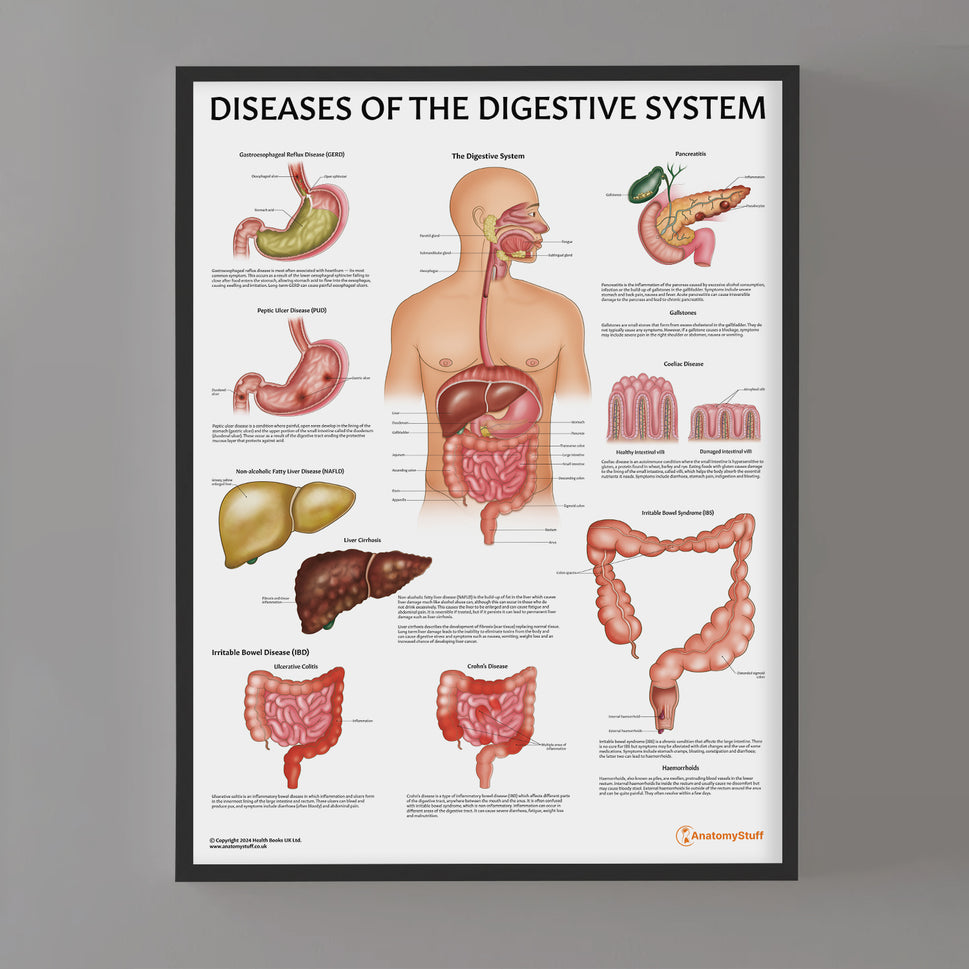

Enhance medical education with our collection of digestive system anatomical models including the stomach, liver, gallbladder, pancreas & colon models. Discover the anatomy of healthy organs as well as common gastrointestinal diseases such as stomach ulcers, gallstones and liver cirrhosis. Our digestive system anatomy posters are ideal for study and patient education.

At AnatomyStuff we stock a diverse range of digestive system anatomical models to suit your training needs. From budget models and affordable medical education posters to highly advanced 3D printed bowel models, you can transform medical training and patient education. As well as our own exclusive collection, we are proud resellers of 3B Scientific, Anatomy Lab, Denoyer-Geppert Science Company, ESP Models, Erler Zimmer and GPI Anatomicals. Explore our exclusive collection of digestive system anatomy charts, posters, fine art prints and digital anatomy study guides. Discover the anatomy of key organs like the liver, stomach, pancreas and bowel as well as the pathophysiology of common conditions like peptic ulcer disease, coeliac disease, IBD and much more. We have anatomy posters suitable for school children all the way up to medical degree level. From a liver anatomy poster to a digital study guide all about common GI disorders, find exactly what you need right here to enhance medical training and patient education.